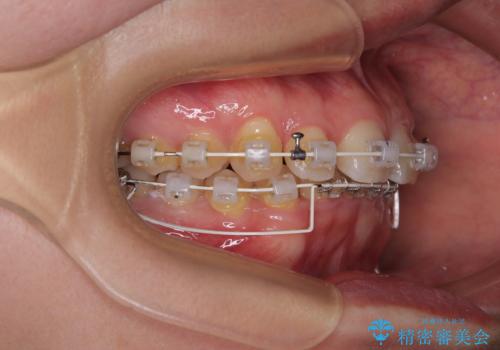

咬合力が強いことと、マウスピースを長時間装着する自信がないとのことで、ワイヤー装置にて矯正治療を行うこととしました。

下顎臼歯を起き上がらせるためにユーティリティーアーチを使用し、一気に深い咬み合わせを改善することができました。